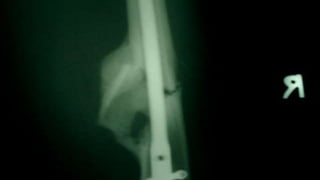

Distal Femur retrograde nailing

Brief steps of distal femoral retrograde nailing of femur